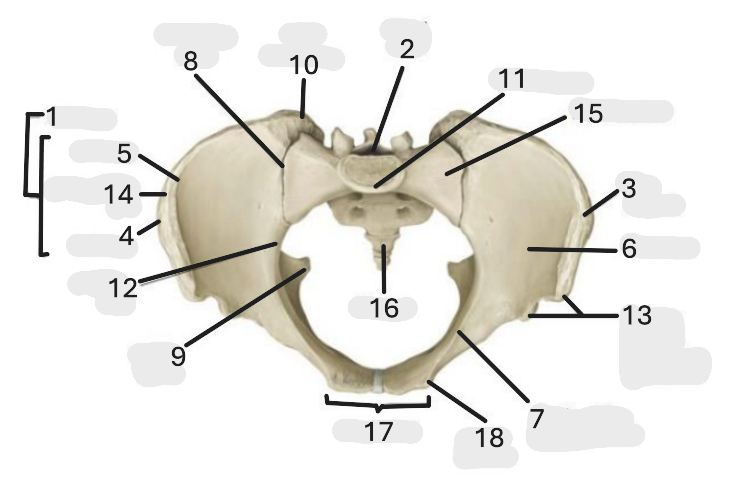

Where is the iliac crest

1

where is the sacral canal

2

Where is the iliac tubercle

3

Where is the outer lip

4

Where is the inner lip

5

Where is the iliac fossa

6

Where is the pectineal line (pecten pubis)

7

Where is the sacroiliac joint

8

Where is the ischial spine

9

Where is the iliac tuberosity

10

Where is the promontory

11

Where is the arcuate line

12

Where is the anterior superior and inferior iliac spine

13

Where is the intermediate line

14

Where is the ala of the sacrum

15

Where is the coccyx

16

Where is the pubic crest

17

Where is the pubic tubercle

18